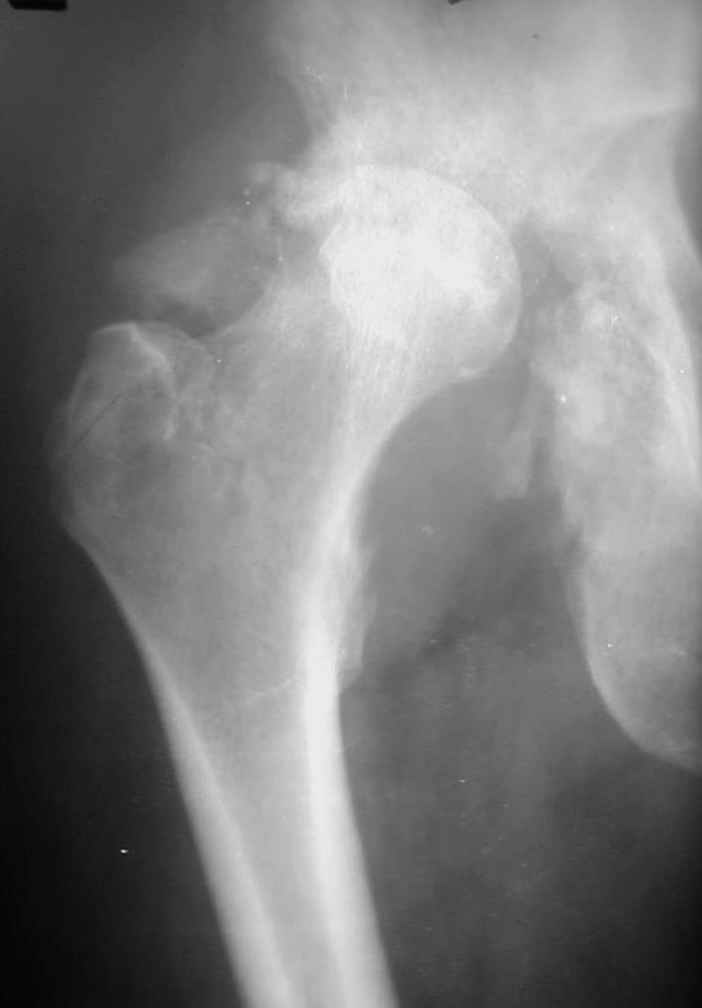

В институте совместно с фирмой Зиммер достаточно регулярно (практически ежемесячно) проводятся 2-х недельные циклы по различным вопросам эндопротезирования. Если есть возможность и желание, мы готовы поделиться с Вами нашим опытом, тем более есть что показать и что обсудить - в настоящее время ежедневно выполняется от 6 до 10 эндопротезирований коленного и тазобедренного сустава. В качестве примеров хочу показать 2 наблюдения, через 1 год и 5 лет после операции

1 год

5 лет